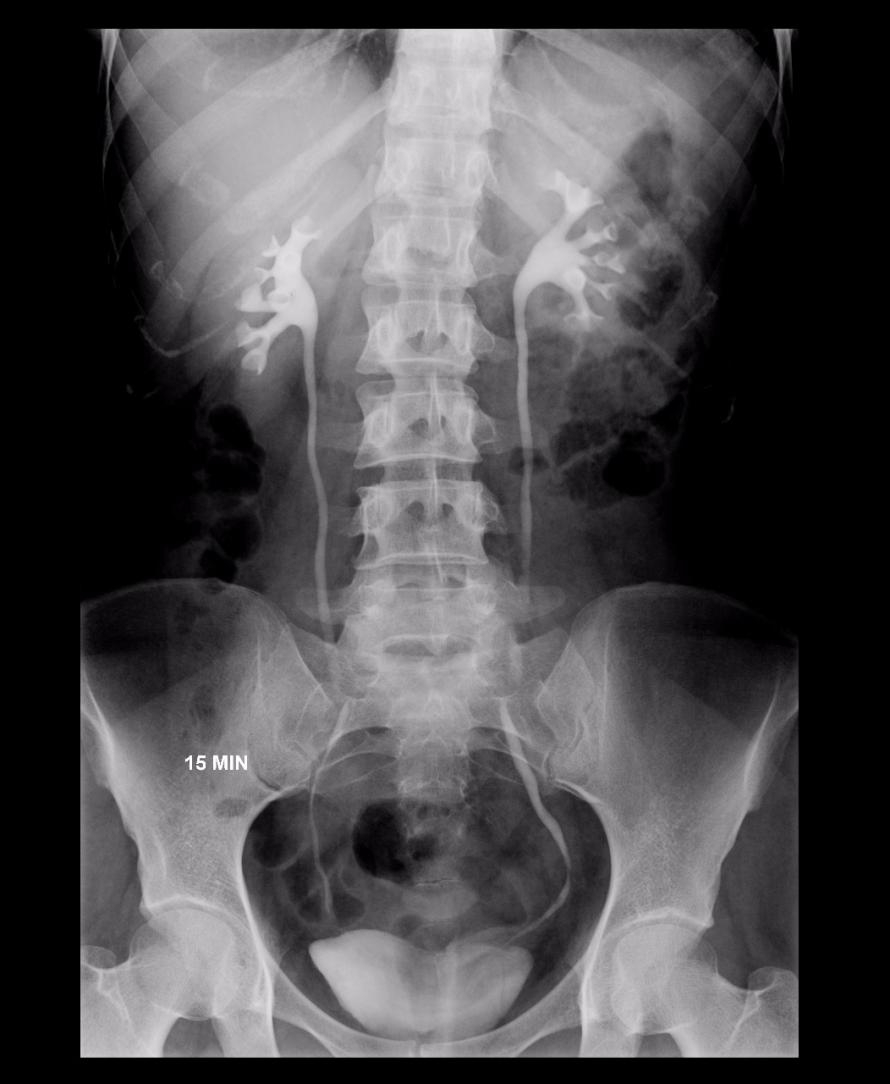

Urografia excretora

- O exame avalia os rins e as vias urinárias, através da injeção de contraste iodado por via endovenosa. O contraste é excretado pelos rins e vias urinárias chegando até a bexiga, permitindo a avaliação dos mesmos.